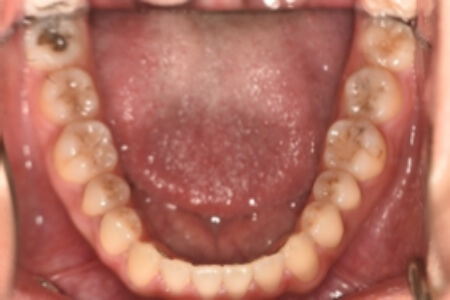

動的治療終了時

検査の結果、上下顎前歯部に空隙を伴うアングルⅠ級不正咬合と診断しました。

治療としては、非抜歯の上、マウスピース矯正装置(インビザライン)で配列を行いました。

治療期間は、1年9か月でした。